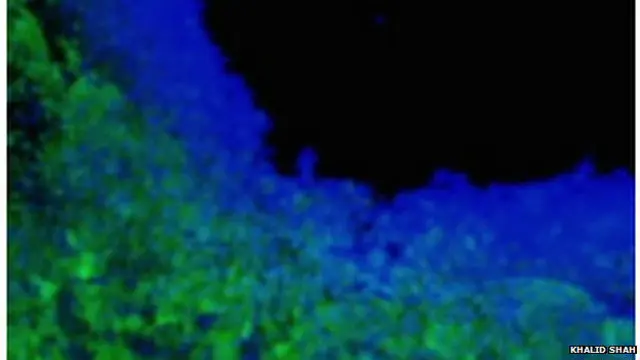

इस ज़हर ने सामान्य और स्वस्थ कोशिकाओं पर बिल्कुल भी असर नहीं डाला.

जानवरों पर किए गए परीक्षण में जैल में घिरे स्टेम सेल को मस्तिष्क में कैंसर वाली जगह पर रखा गया था जिसे बाद में हटा दिया गया.

इसके असर से कैंसर कोशिकाएं मृत हो गईं क्योंकि इनके पास इस ज़हरीले पदार्थ से बचाव के लिए कुछ भी नहीं था.